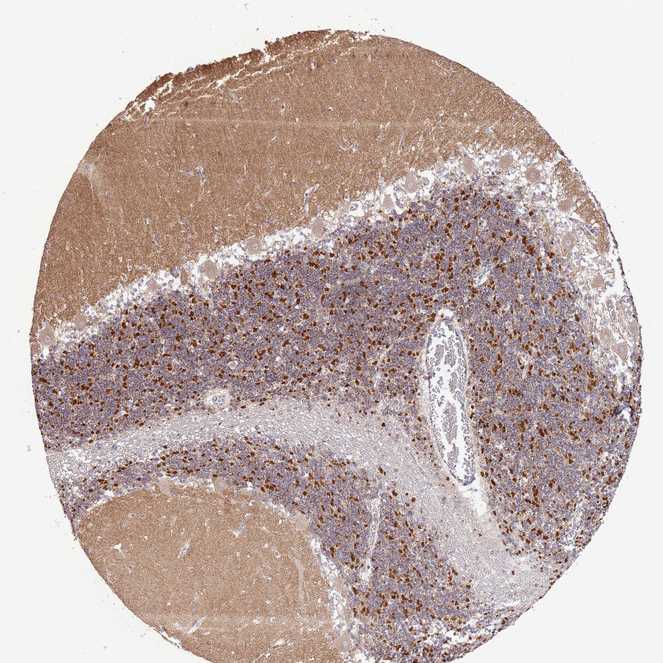

CEREBELLUM - Antibody stainingi

Antibody staining in the annotated cell types in the current human tissue is reported as not detected, low, medium, or high, based on conventional immunohistochemistry profiling in selected tissues. This score is based on the combination of the staining intensity and fraction of stained cells.

Each image is clickable and will lead to virtual microscopy that enables deeper exploration of all samples and also displays staining intensity scores, fraction scores and subcellular localization as well as patient and tissue information for each sample.

Antibody HPA041928Antibody HPA043537

Purkinje cells Not detectedLow

Cells in granular layer Not detectedHigh

Cells in molecular layer Not detectedNot detected